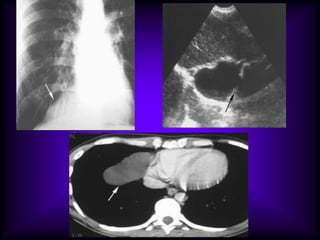

Ultrasonography (US) can be useful in

evaluating a mass adjacent to the

pleural surface or cardiophrenic angle.

At US, the benign cysts typically

appear as anechoic thin-walled

masses with increased through

transmission